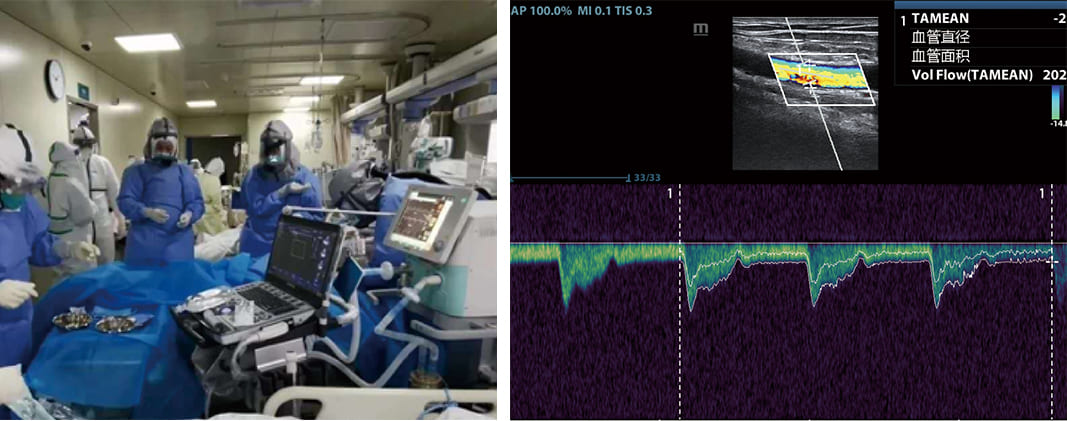

3. ECMO Support

Extracorporeal membrane oxygenation (ECMO) is a life-saving technique in critical care, particularly for patients with severe cardiac or respiratory failure. Portable ultrasound devices support ECMO procedures by assisting in vascular punctures. Clinicians can use ultrasound to locate and visualize arteriovenous vessels, thus improving the efficiency and safety of this surgical procedure. This innovation has been a significant boon to ECMO, a technique that requires precision and accuracy.

In the context of ECMO, a procedure that requires precise vascular access, portable ultrasound offers a safe and efficient solution. By visualizing arteriovenous vessels in real-time, clinicians can minimize complications and enhance the success rate of ECMO initiation.